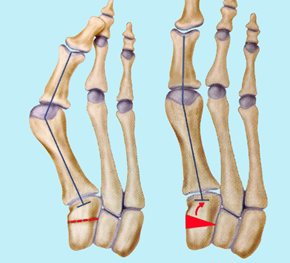

5. 骨骺闭合术 在儿童外翻,可以使用骑缝钉固定阻滞第1跖骨基底外侧骨骺生长的方法达到纠正第1跖骨内翻的目的。取出骑缝钉恢复骨骺生长。同时结合跖骨远端截骨术和软组织手术。